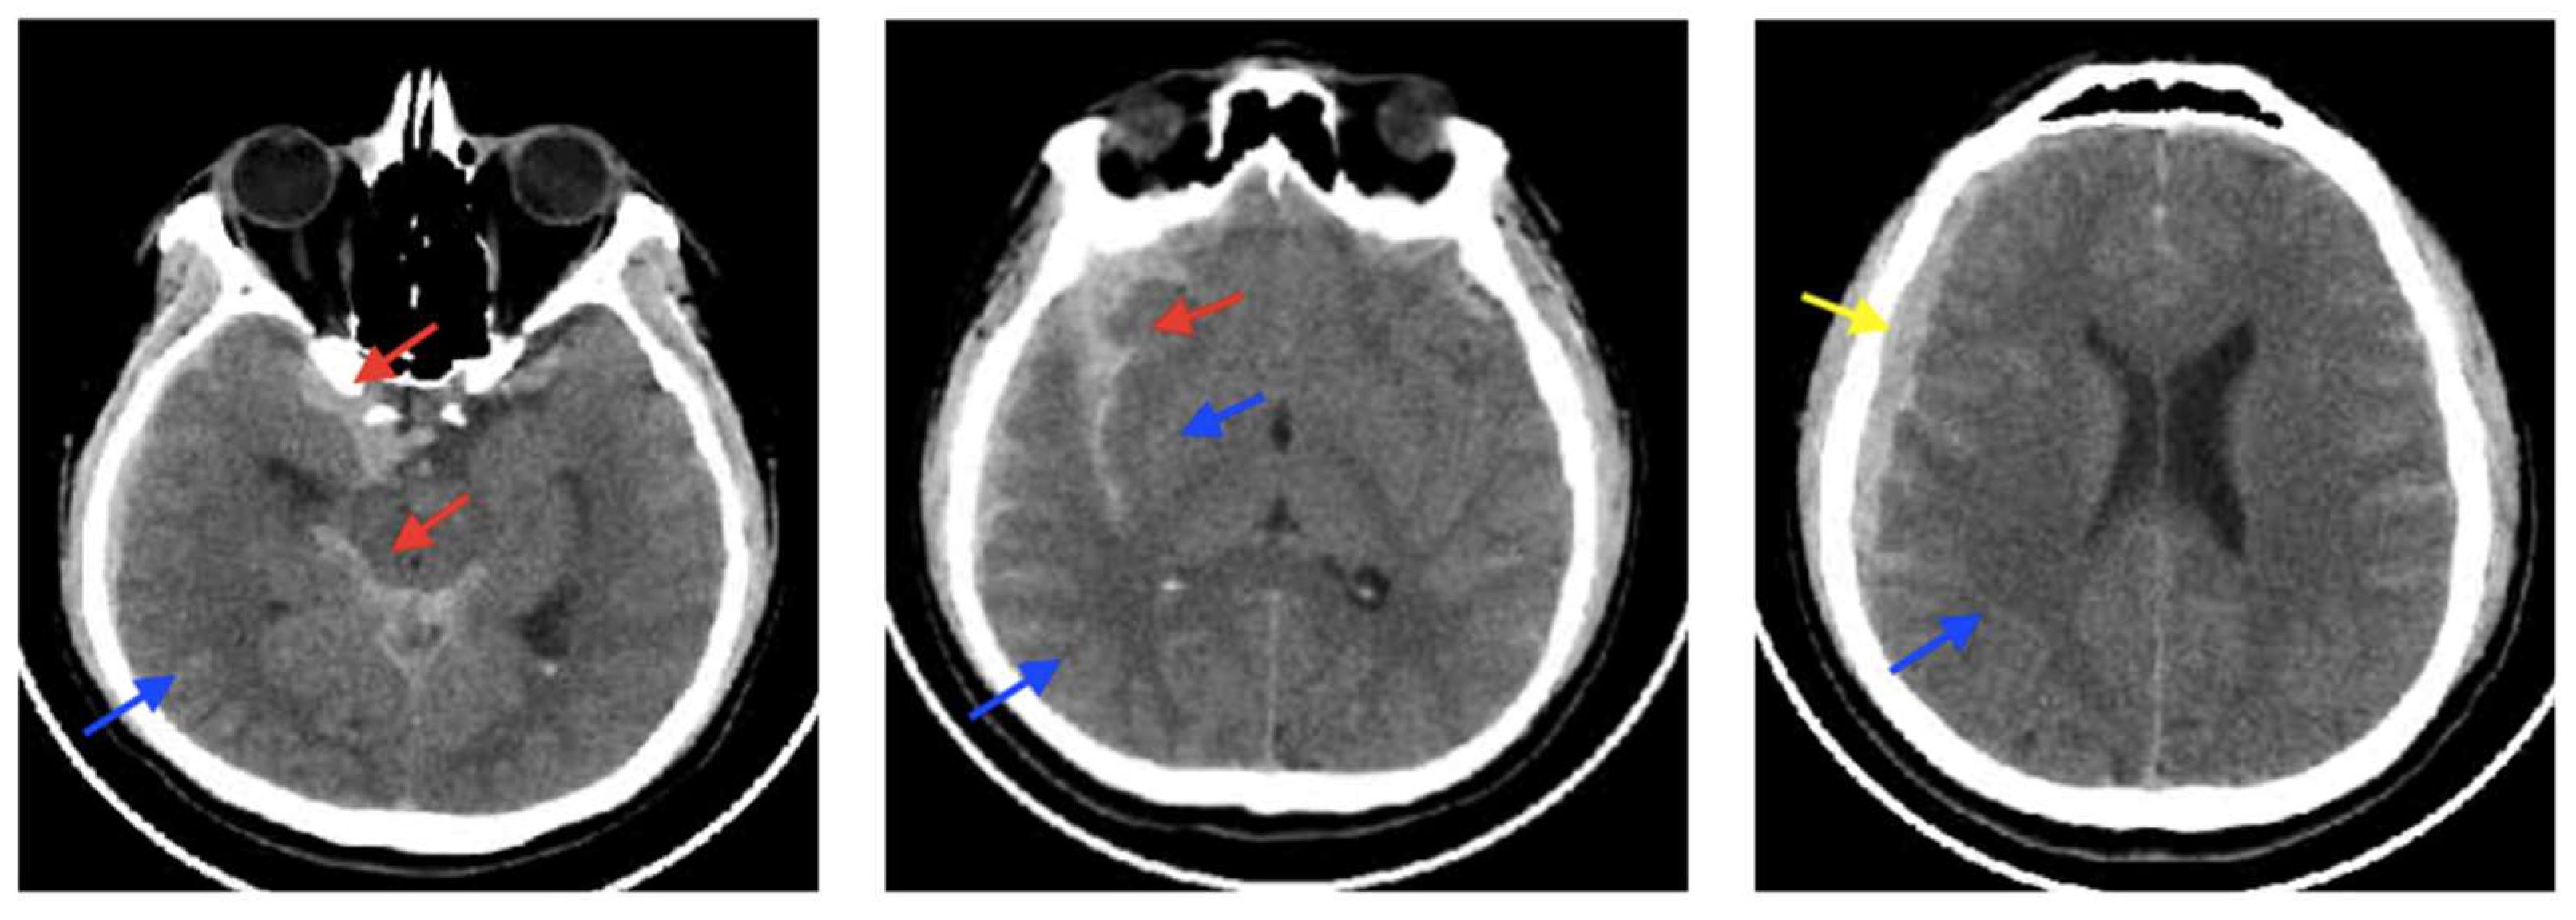

3.6. CSF-Shift Edema

| CSF-Shift | Preserved | Interstitial | CSF/Water and ions | Fluid accumulation in the interstitial space occurs when CSF moves from the subarachnoid cisterns to the brain’s interstitial space through VRS due to increased pressure in the brain cisterns from conditions like subarachnoid hemorrhage. | Cisternostomy as solely early intervention or as coadjuvant therapy when performing a craniotomy or craniectomy for hematoma drainage or brain edema control. |